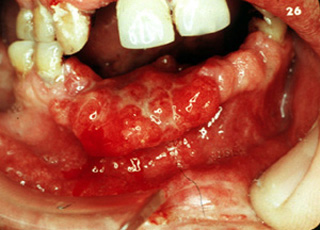

Carcinoma verrugoso

Aquí son evidentes las áreas focales múltiples de carcinoma, que involucra

la mucosa bucal. Algunos de éstos tienen una forma clinica de verruga; de hecho, éste es una de las áreas más comúnes para la ocurrencia del carcinoma

verrugoso. |